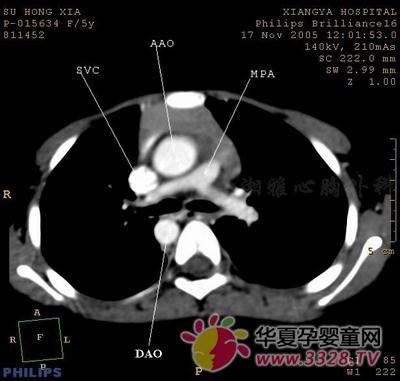

肺動(dòng)脈瓣狹窄

先天性肺動(dòng)脈狹窄是右心室到肺動(dòng)脈血流受阻的疾病,也是較為常見(jiàn)的一種先天性心臟病。肺動(dòng)脈瓣畸形狹窄可分為輕度、中度和重度,長(zhǎng)期的中重度肺動(dòng)脈瓣狹窄會(huì)導(dǎo)致右心功能的減退,出現(xiàn)右心衰竭。但輕度肺動(dòng)脈瓣狹窄的寶貝,如平時(shí)無(wú)明顯紫紺、嚴(yán)重缺氧、喂養(yǎng)困難、心功能衰竭等癥狀,發(fā)育也正常,定期到醫(yī)院檢查、動(dòng)態(tài)觀(guān)察心臟變化即可。隨著寶貝的發(fā)育,肺動(dòng)脈狹窄也可能有所緩解,寶貝可正常生長(zhǎng)發(fā)育并具有正常的生活能力。

對(duì)于中度和重度肺動(dòng)脈瓣狹窄的寶貝,必須進(jìn)行介入治療和手術(shù)治療,首選的治療方法是應(yīng)用球囊導(dǎo)管擴(kuò)張狹窄的肺動(dòng)脈瓣,這種方法利用球囊內(nèi)壓所產(chǎn)生的張力而擴(kuò)張狹窄的瓣口,可使寶貝免去因開(kāi)胸帶來(lái)的手術(shù)創(chuàng)傷和痛苦,并減輕家長(zhǎng)的精神和經(jīng)濟(jì)負(fù)擔(dān),而且療效好,并發(fā)癥少。對(duì)于少數(shù)嚴(yán)重肺動(dòng)脈瓣狹窄的寶貝,則需施行開(kāi)胸手術(shù)切開(kāi)狹窄的瓣膜矯治畸形,以達(dá)到根治的目的。